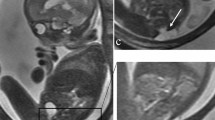

When possible, we chose SSFP sequences over T2-W sequences because of their superior umbilical vessel/eventration contrast. Volumetry was performed on a single plane, preferentially on transverse over sagittal orientation. We conducted the manual segmentation of eventrated organ volume, intraabdominal volume and total fetal volume using the open-source software application ITK-SNAP version 3.6.0 [20] (Fig. 2). Eventrated organ volume was identified and mapped first. To ascertain that umbilical vessels were not falsely labeled as eventrated intestine, we visually tracked the umbilical vessels from the placenta to the abdominal insertion. We determined the transition from eventrated organ volume to intraabdominal volume to be the plane where ventral abdominal muscle would have closed the abdominal cavity. Intraabdominal volume was mapped with the following anatomical borders. The superior boundary was formed by the thoracic cavity, respectively the diaphragm; delineation of intraabdominal organs from lung and heart was excellent, which in turn provided accurate mapping. The inferior border was defined at the height of the urinary bladder, which was not included in the intraabdominal volume; the kidneys were included in the intraabdominal volume. Anterior and lateral limits were the muscles of the abdominal wall. The posterior border was defined as the quadratus lumborum and psoas muscles as well as the spine, none of which was included in the intraabdominal volume. Figure 3 shows an example of the full volume in three dimensions. Full segmentation took approximately 100 min per subject on average. Segmentation of the intraabdominal and eventrated organ volume took about 20 min or less in most cases, while segmentation of total fetal volume took about 80 min.

A three-dimensional overview of the same fetus as in Fig. 2 after full volumetry. The fetus is seen in red with the eventrated bowel between extremities and head seen in blue. Intraabdominal volume cannot be seen on this graphic